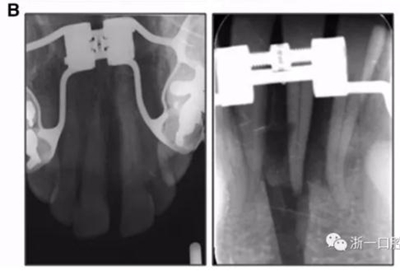

全麻下進行上頜骨腭中縫骨皮質劈開及下頜正中劈開術。手術后,用X光片檢查上頜骨和下頜骨中線切口的位置和方向。

術后第9天開始旋轉擴弓器,每天轉2次,每次轉90度,即擴開0.5mm。每隔1周進行檢查,目標上頜擴開9mm,下頜擴開6mm。18天后,上頜中切牙間出現8mm間隙。下頜出現6mm間隙,(于13天出現后,停止旋轉擴弓器)。在擴弓器旋轉3天后,拍片發(fā)現左下頜中切牙遠中牙根中段有一條低密度陰影,臨床冷熱診反應遲鈍,可能為術中損傷所致。牙體牙髓科會診,建議行根管治療,故行根管治療。